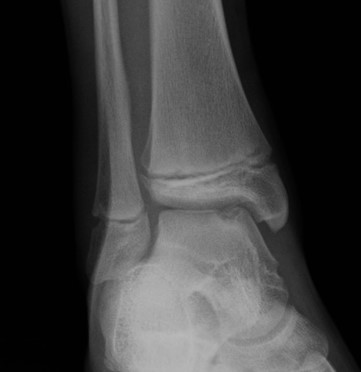

Fugengelenkfrakturen treten typischerweise vor dem 10. Lebensjahr auf, in einer Phase, in welcher die Wachstumsfugen noch weit offen sind. Dieser Frakturtyp betrifft fast ausschließlich den medialen Malleolus. Laterale Frakturen sind extrem selten, teilweise kommt es zu lateralen Bandverletzungen oder Fugenschaftfrakturen der distalen Fibula. Die Frakturlinie verläuft in einer Verlängerungslinie von der medialen Taluskante nach proximal. Häufig stellen sich Verletzungen des Innenknöchels im Röntgenbild schlechter dar, insbesondere wenn die Aufnahmen verdreht sind oder die Ebene der Fraktur bei geringer Dislokation verkippt zur Röntgenebene liegt. Besteht klinisch der geringste Hinweis auf eine Verletzung des Innenknöchels, muss aufgrund der Tragweite der Verletzung durch entsprechende Aufnahmen gegebenenfalls auch Schnittbildverfahren die Verletzung sicher diagnostiziert oder ausgeschlossen werden (Abb. 15).

„Kadiläsion“- Mediale Malleolarfraktur

Bei kindlichen Verletzungen des medialen Malleolus handelt es sich nach L. v. Laer um eine sogenannte Kadiläsion, d.h. eine Verletzung mit hohem Risiko eines schlechten Behandlungsergebnisses bei nicht korrekter Behandlung. Selbst bei optimaler Therapie ist das Risiko für spätere Wachstumsstörungen hoch, sodass diese Verletzungen nicht selten ein juristisches Nachspiel haben. Durch die Verletzung der wachstumsaktiven Zone kann es zu einem vorzeitigen Verschluss der Wachstumsfuge kommen, mit entsprechendem Fehlwachstum. Das Risiko eines vorzeitigen Verschlusses der Wachstumsfuge korreliert mit dem Ausmaß der Schädigung der wachstumsaktiven Zone. Ab dem 13. Lebensjahr wird das Risiko bei reduzierter Wachstumsaktivität zunehmend geringer.

Fugengelenkfrakturen können die Wachstumsfuge durchkreuzen (Abbildung 16a), ohne oder nur mit minimaler Beteiligung der Fuge sehr weit medial liegen (Abbildung 16b) oder durch die Fuge auslaufen (Abbildung 16c). Relevant für die Wachstumsprognose ist weniger die Form der Fraktur, sondern das Alter des Patienten zum Zeitpunkt des Traumas sowie das Ausmaß der Schädigung der Wachstumsfuge, wobei eine Korrelation mit dem Ausmaß der Dislokation besteht.